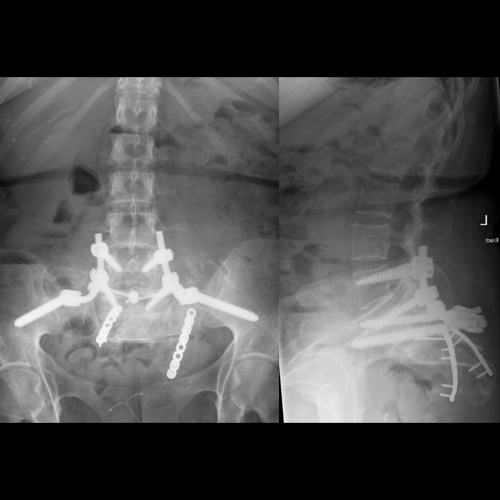

Spinal stenosis (Lumbar) Spinal stenosis (Cervical) Spinal stenosis (Thoracic) Lumbar Disc Herniation Spondylolisthesis Cervical Foraminal Stenosis Vertebroplasty Lumbar Fusion Anterior Cervical Fusion (ACDF) Posterior Cervical Fusion Thoracic Fusion Revision Lumbar Fusion Surgery Facet Joint Cyst Spinal Tumour Minimally Invasive Lumbar Fusion (XLIF) Minimally Invasive Lumbar Fusion (ALIF) Lumbar Fusion (TLIF) Thoraco-lumbar Fusion Lumbar Corpectomy Complex Lumbar Spine Surgery (Spino-pelvic fixation) Complex Cervical Spine Surgery Complex Thoracic Spine Surgery Occipito-cervical Fusion Minimally invasive surgery for thoracic disc herniation Other Related Topics